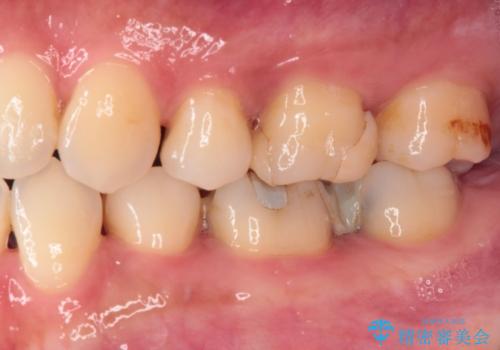

手前の歯はむし歯の範囲が広いためオールセラミッククラウンにて、最後方歯は部分的なむし歯であったのでPGAインレー(プラチナゴールドインレー)にて治療を進めることとしました。

仮詰めの状態が良くなかっただけで、むし歯が神経組織にまで及んでいることはなく、無事に治療を終えることができました。